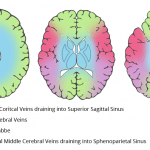

- Hyperdensity in the left transverse sinus, straight sinus, vein of Galen, and in veins coursing along the left cerebellar hemisphere

- Scattered linear hyperdensities within sulci in the bilateral cerebral and cerebellar hemispheres

- Venous sinus thrombosis with associated hemorrhage and parenchymal edema

Hyperdensity in the left transverse sinus, straight sinus, vein of Galen, and in a vein coursing along the left cerebellar hemisphere concerning for venous thrombosis. Small acute parenchymal hemorrhage in the high right frontal lobe raises concern for superior sagittal sinus and/or cortical vein thrombosis as well. Recommend brain MRI with and without contrast for further evaluation.

Scattered linear hyperdensities within sulci in the bilateral cerebral and cerebellar hemispheres, which may represent small volume subarachnoid hemorrhage and/or additional small thrombosed veins. No hydrocephalus.